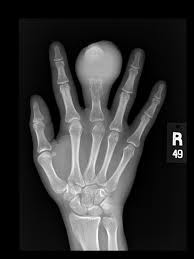

5. U xương: khối u tế bào nhỏ, tròn phát sinh trong xương hoặc các mô mềm. Thường được tìm thấy trong cánh tay, chân, xương chậu (xương hông) hoặc ngực.

6. U xương ác tính: hình thức phổ biến nhất của ung thư xương ở trẻ em. Nó xảy ra thường xuyên nhất trong xương ở chân hoặc ở cánh tay .